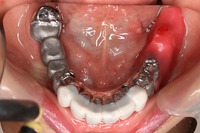

リーゲルレバーを閉じたところです。

お口にしっかりと固定され、びくともせずにしっかりと咬むことが出来ます。